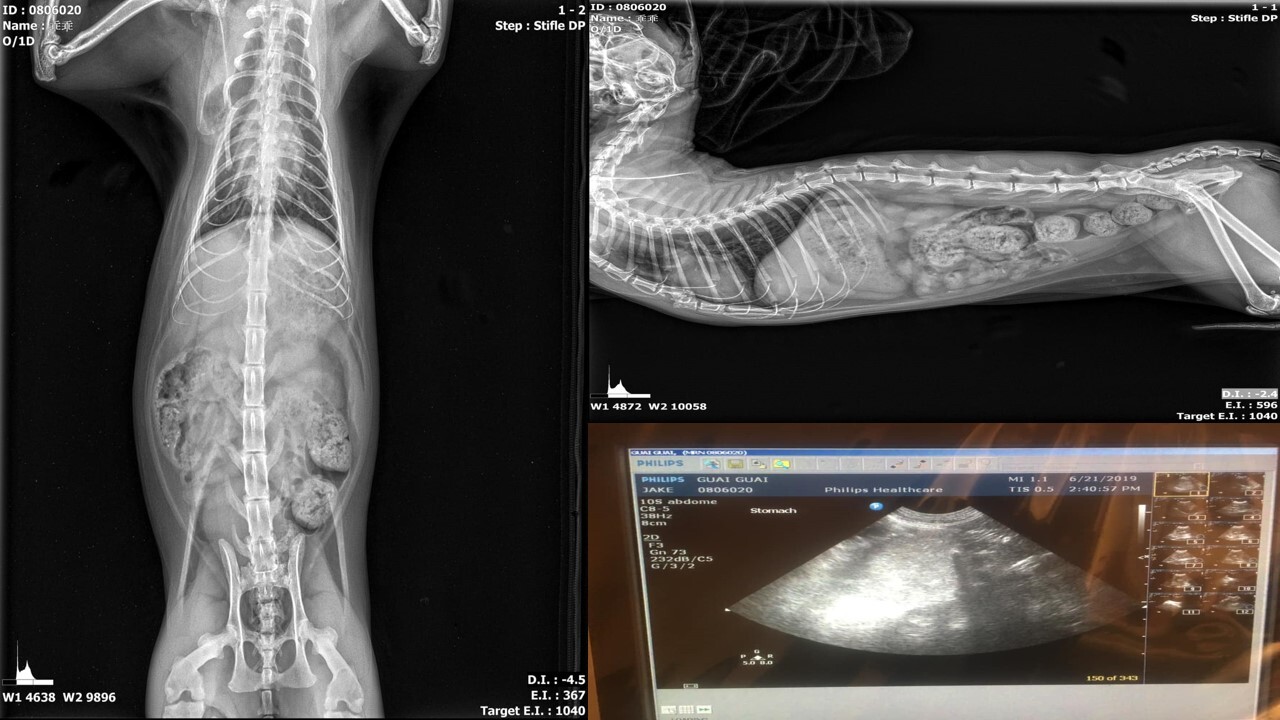

主題: 乖乖病情不穩定,回診發現內出血,緊急配血輸血 申請者姓名: 李韋慶 花色: 申請日期: 2019-09-25 22:40:20 申請者部落格: 申請者臉書網址: https://www.facebook.com/azmailmouse 所在縣市/合作醫院: 台北市/沐恩動物醫院 治療費用: 186548元 需求人數: 399人 已結案 (2024-05-31 18:26:10) 報名人員: Alumi Lu(已付款)、沒有這個人(已付款)、Katherine Yim x2(已付款)、郭默(已付款)、Olga(已付款)、may(已付款)、Ciara Ting(已付款)、Ciara Ting(已付款)、jili(已付款)、Daniel Tsai x6(已付款)、kimi(已付款)、FaFa(已付款)、SY Liou(已付款)、Freesia Tsai(已付款)、Wei(已付款)、Vivianeliao x2(已付款)、Anny Jan(已付款)、wgs(已付款)、典媽 x5(已付款)、Vic Wei(已付款)、May x4(已付款)、張雅筑 x2(已付款)、蔡Tina(已付款)、小咪毛(已付款)、Ju-Yun Hsu(已付款)、Alice Tsai x2(已付款)、Zoe Peng x2(已付款)、逗點(已付款)、Naommi x3(已付款)、Ago Walker(已付款)、游玉娘(已付款)、caryko x2(已付款)、王豆乾(已付款)、阿峯(已付款)、鹿兒島 x6(已付款)、Mia Chao(已付款)、Helen(已付款)、藍卡姆(已付款)、周星星 x2(已付款)、ying(已付款)、張倚瑄(已付款)、張倚瑄(已付款)、meemee(已付款)、Pearl Hsu(已付款)、Emma Liao x2(已付款)、Elena(已付款)、SY Liou(已付款)、Kaizan x2(已付款)、Charkao(已付款)、Ann(已付款)、劉熊妹(已付款)、匿名(已付款)、劉俊平(已付款)、FaFa(已付款)、辜曉薇 x2(已付款)、joanna x2(已付款)、Masaki x2(已付款)、Francia x2(已付款)、小黃(已付款)、小黃、Teresa Lai(已付款)、迷迷(已付款)、Yi Hsuan Chen(已付款)、Shoot Yo(已付款)、Kathy Lee(已付款)、光 x20(已付款)、bluefox(已付款)、林廷軒(已付款)、楊x琳 x8(已付款)、SHan035(已付款)、林小黑(已付款)、apple x4(已付款)、coruby x2(已付款)、Grass(已付款)、Mercury Tseng(已付款)、劉安柏 x2(已付款)、MAY x2(已付款)、citin(已付款)、舒婷(已付款)、陳昱先 x2(已付款)、Laura Chen(已付款)、victor shen(已付款)、Soda Yeh(已付款)、Emma Su(已付款)、Lucy(已付款)、Emily(已付款)、ying(已付款)、kate(已付款)、陳昱先 x2(已付款)、Violet Chang(已付款)、吳斑比 x2(已付款)、坑長(已付款)、FaFa(已付款)、MJ(已付款)、一杯水 x2(已付款)、Gracelue x2(已付款)、胖胖姐姐 x2(已付款)、鄭家琪 x2(已付款)、Anny Jan(已付款)、張雅筑 x2(已付款)、掩日(已付款)、劉熊妹(已付款)、伶人 x4(已付款)、凱蒂娟(已付款)、Viola Yu x2(已付款)、Sarah Xie(已付款)、Julian(已付款)、Yen-Yuan Wang(已付款)、Genrei Chen(已付款)、海郁 x2(已付款)、W.Y ONLINE STORE(已付款)、瓦莉阿嬤(已付款)、Joe G(已付款)、羅柚子 x2(已付款)、羅柚子、羅柚子 x2(已付款)、Nadia Wang(已付款)、Andrea Hsieh(已付款)、Shoot Yo(已付款)、Ju-Yun Hsu(已付款)、罐頭(已付款)、辜曉薇愛 x4(已付款)、辜曉薇愛 x4、涂拼奇(已付款)、陳栗子 x6、River Ho x4(已付款)、福祿壽(已付款)、Jessie Kuo(已付款)、Justina(已付款)、emma x2(已付款)、Jenna(已付款)、趙嘉馨 x2(已付款)、JEFF x4(已付款)、Joan(已付款)、Andy chen(已付款)、SY Liou(已付款)、Tobey、Ling Lan(已付款)、Mia Chao(已付款)、Sylvia Tsai x2、小靜 x2(已付款)、YUYU x2(已付款)、Sylvia Tsai x2(已付款)、amy x2(已付款)、卓卓(已付款)、坑長 x2(已付款)、hsinkai0407 x2(已付款)、Caine x2(已付款)、楊亞蒨 x2(已付款)、劉熊妹(已付款)、無名氏(已付款)、瓦莉阿嬤(已付款)、黃耀賞(已付款)、Jamie(已付款)、safake x2(已付款)、嘟哇李(已付款)、小玉(已付款)、mint x2(已付款)、厚 x3(已付款)、君君(已付款)、育升居家修繕工程行(已付款)、lsf330(已付款)、Jasmine Lin(已付款)、Dorothy Ho x2(已付款)、肥仔貓(已付款)、Niki(已付款)、蔡茶茶 x2(已付款)、Kaoru Lin(已付款)、白婷(已付款)、白婷(已付款)、紫戀(已付款)、紫米糕(已付款)、小賴(已付款)、Kathy Lee(已付款)、Alicia(已付款)、Jou x2(已付款)、Evie(已付款)、林小蝦(已付款)、Maria Tu(已付款)、淇(已付款)、陳嘉莉 x2(已付款)、Carambar Liu(已付款)、Little Cat Chang(已付款)、River Ho x6(已付款)、River Ho x6、wgs(已付款)、福祿壽 x2(已付款)、cia(已付款)、簡艾倫(已付款)、小萌(已付款)、JUN(已付款)、洪凱威(已付款)、Demi(已付款)、林廷軒(已付款)、何偉靖 x5(已付款)、yutinglin x2(已付款)、姵玲(已付款)、咪寶寶的阿木 x2(已付款)、丫丫 x3(已付款)、Tzu Ning Kuo x4(已付款)、Ellen Lu x2(已付款)、吳小小(已付款)、Yu-hsien Huang x10(已付款)、Pearl Hsu(已付款)、Pei Hsuan Chiang(已付款)、someme x2(已付款)、may x2(已付款)、黛咪 x3(已付款)、Joan(已付款)、黑貓嘛(已付款)、Mona’ cafe寵物餐廳 x2(已付款)、HTLE(已付款)、Laura(已付款)、Jackie Chao(已付款)、Patrick x6(已付款)、祝福乖乖 加油 x3、Mei Mei Liao x2(已付款)、Nana Wu x2(已付款)、廖瓊華(已付款)、Ellery x10(已付款)、Coleen Chao、邱紫戀 x2(已付款)、Glow x4(已付款)、Rachel Hsiao(已付款)、靖芳(已付款)、張雅筑(已付款)、Andy chen(已付款)、tina(已付款)、ali x2(已付款)、Mui x19(已付款)、楊亞蒨(已付款)、 候補人員: 動物病情說明: 乖乖,尚未找到病灶,病情不穩定,多次往返醫院與住院,一次回診發現內出血,緊急配血與輸血,穩定病情。

6/12 回診,血檢、腹部超音波與X光檢查,狀況不好,住院治療觀察。(6/12~6/18)

7/29 回診發現內出血,晚間轉診至伊甸動物醫院輸血,穩定病情。

8/22 進行腹腔手術檢查與採樣送檢,找出內出血原因與病灶。動物近況說明: 乖乖因精神不好回診發現內出血,做了X光與超音波檢察卻未發現病灶,因為乖乖狀況複雜且血檢指數顯示身體不好,所以醫院先以輸血與內科方式穩定病情。

8/22開腹檢查與採樣體送檢,待結果出來,再給予最適當的治療方式。